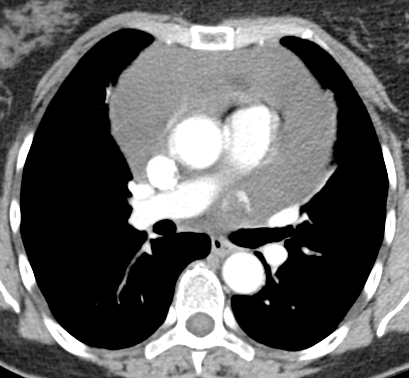

Cardiothoracic surgery was contacted for a pericardial window and biopsy. A repeat contrast enhanced chest CT scan suggested an 18 x 16 mm peripherally enhancing intrapericardial mass, with central low attenuation between the main pulmonary artery and the left atrial appendage. The pericardial effusion was massive, the pericardium was mildly thickened, and a right apical 3 mm pulmonary nodule was evident (Fig. 3).

No cases of isolated pericardial hemangioma were identified by the authors’ searches. The fold of Marshall is a remnant of the left superior vena cava-coronary sinus junction, so the occurrence of a vascular tumor in this location is curious. This patient’s cardiac anatomy was unremarkable, and the apparently unique pericardial tumor was identified only after a contrast CT was done to investigate the status of the pericardial cavity, pericardium, and its contents after rapid recurrence of a massive effusion. The characteristic CT appearance suggested a vascular type of tumor. Coronary angiography was not done because of the patient’s age and lack of angina. After achieving stable exposure, this patient’s resection was simple and margins were clear. Despite its varied and uncertain clinical behavior, complete excision is considered the standard of care, and a favorable outcome is anticipated. Heart transplantation has also been done for a large cardiac hemangioma. It is notable, however, that reports of hemangiomas in other locations describe spontaneous resolution (7), or disappearance after steroid administration (8).